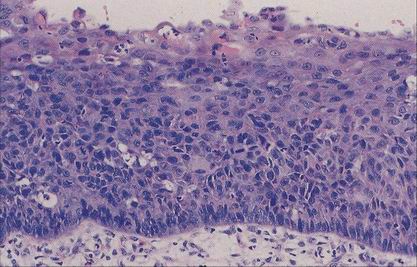

Verrucous carcinoma

Varianta spinoca s velmi dobrou prognózou

Definován

verukózním růstem

minimálním stupněm cytologické atypie

ostře ohraničeným růstem proti spodině (byť může infiltrovat hluboko)

Diagnózu VC z probatorní excize není možno podle uvedené definice stanovit, lze jen vyslovit suspekci.